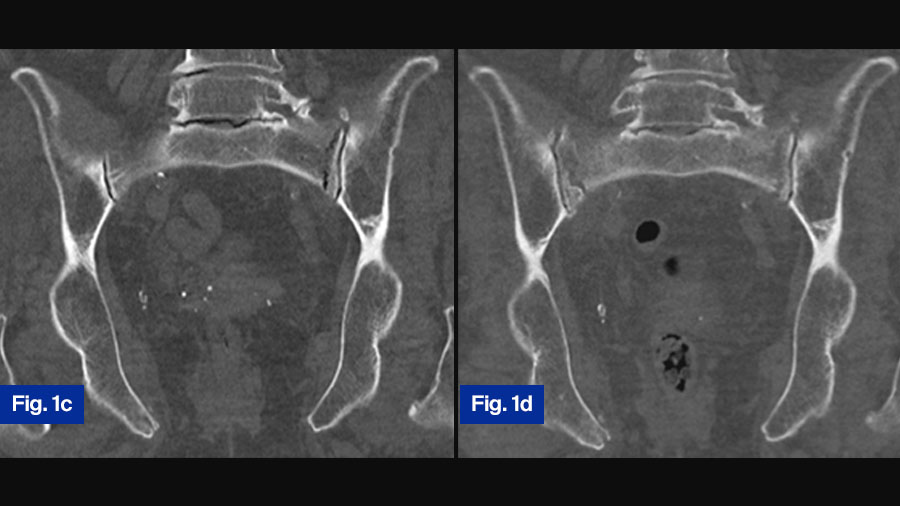

Case study 1: 78-year-old female with progressive fragility fracture

Fig. 1. A seventy-eight-year-old female suffered a domestic fall. The pelvic inlet (a) revealed a slightly displaced fracture of the right pubic ramus. A pelvic CT was taken to exclude fractures of the posterior pelvic ring. On the coronal reconstruction of the posterior pelvis (b), no fracture can be detected. The fracture was classified as FFP Type Ia and conservative treatment initiated.

Due to persisting pain, a second CT was taken one month later. On the coronal reconstruction of the posterior pelvis, a non-displaced fracture of the lateral mass of the sacrum on the left side was now visible (c). Conservative treatment was continued. Because of persistent pain with restricted mobility, a third pelvic CT was taken one month after the second.

The coronal reconstruction of the posterior pelvis revealed an additional fracture of the lateral mass of the sacrum on the right side (d). The fracture progressed from FFP Type Ia to FFP Type IIc.